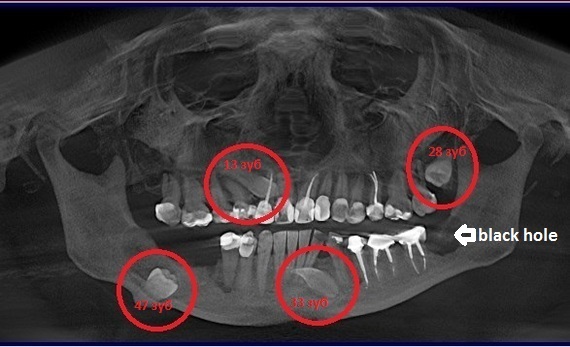

Дентальная галерея: ретинированный зуб клык и его лечение

Раздел: Компас решений